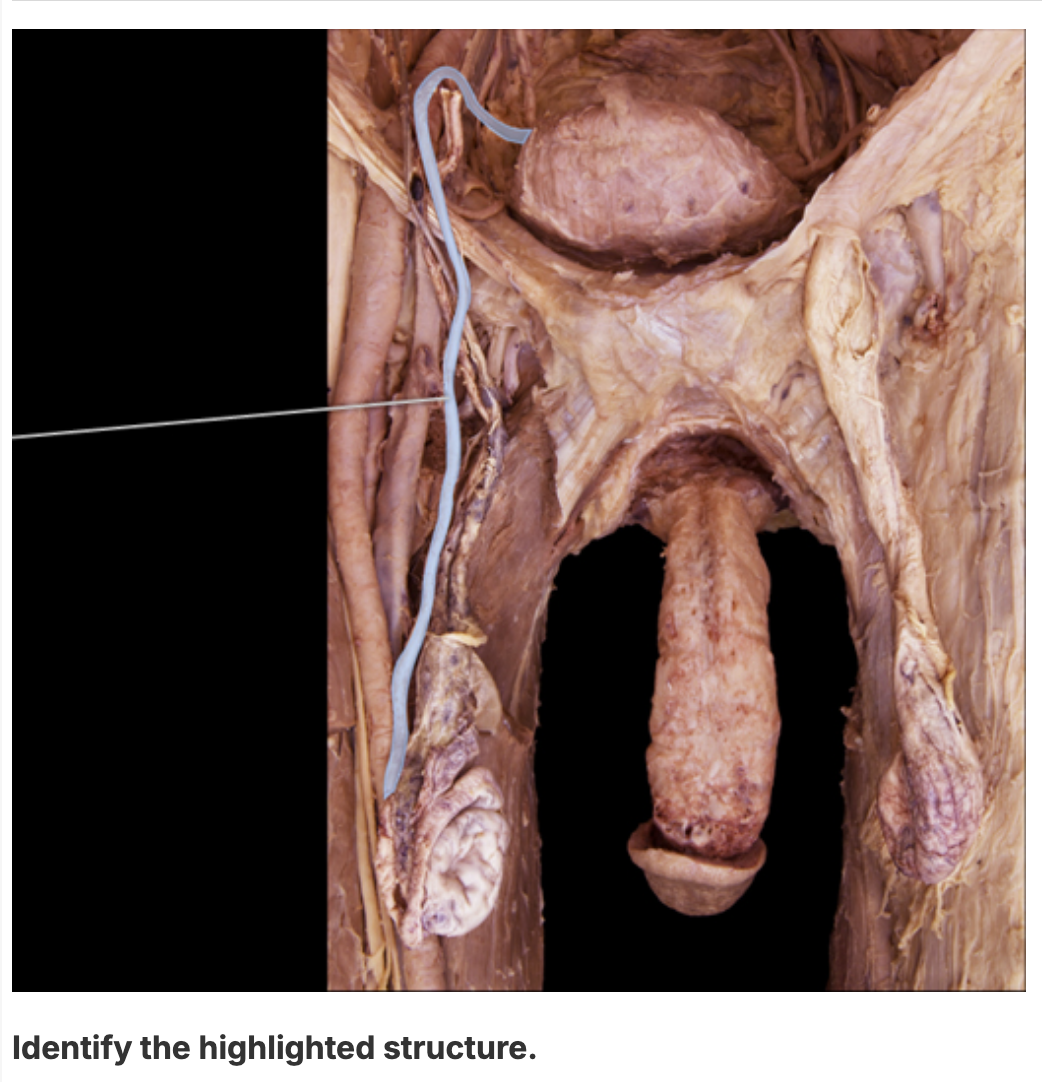

ductus deferens